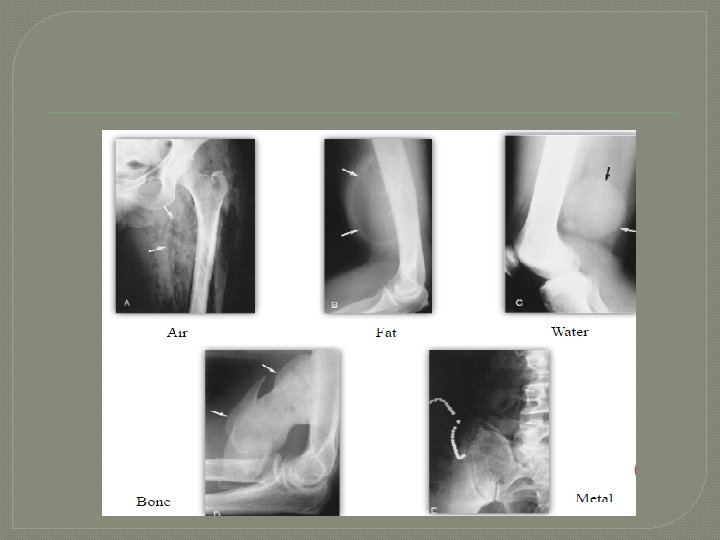

Conventional imaging Basic densities

Two views are required